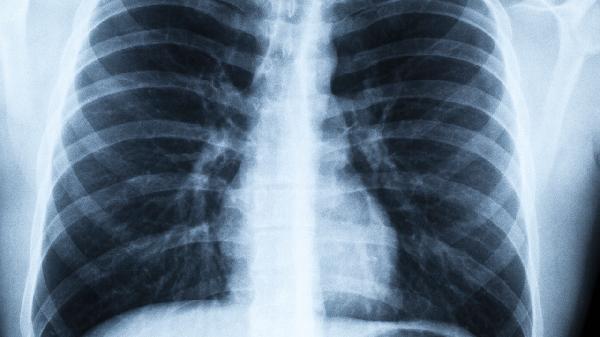

吸烟者、有呼吸系统疾病史者更易发病。定期进行高千伏胸片检查和肺功能检测有助于早期发现。